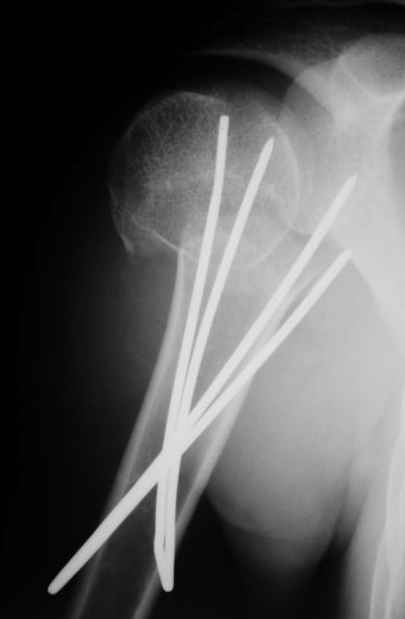

Коллеги, Больной прооперирован вчера. 19 летний пациент с переломом шейки плеча. Закрытая репозиция и чрескожная фиксация спицами под контролем ЭОПа ( техника проф. Лазарева)

Интраоперационный контроль на стабильность фиксации - сомнений в стабильности фиксации не возникло. Послеоперационный контроль сегодня......

Необходимость послеоперационного Рг контроля..... Больной запланирован на повторную манипуляцию и транспозицию спиц Евгений И Чекашкин